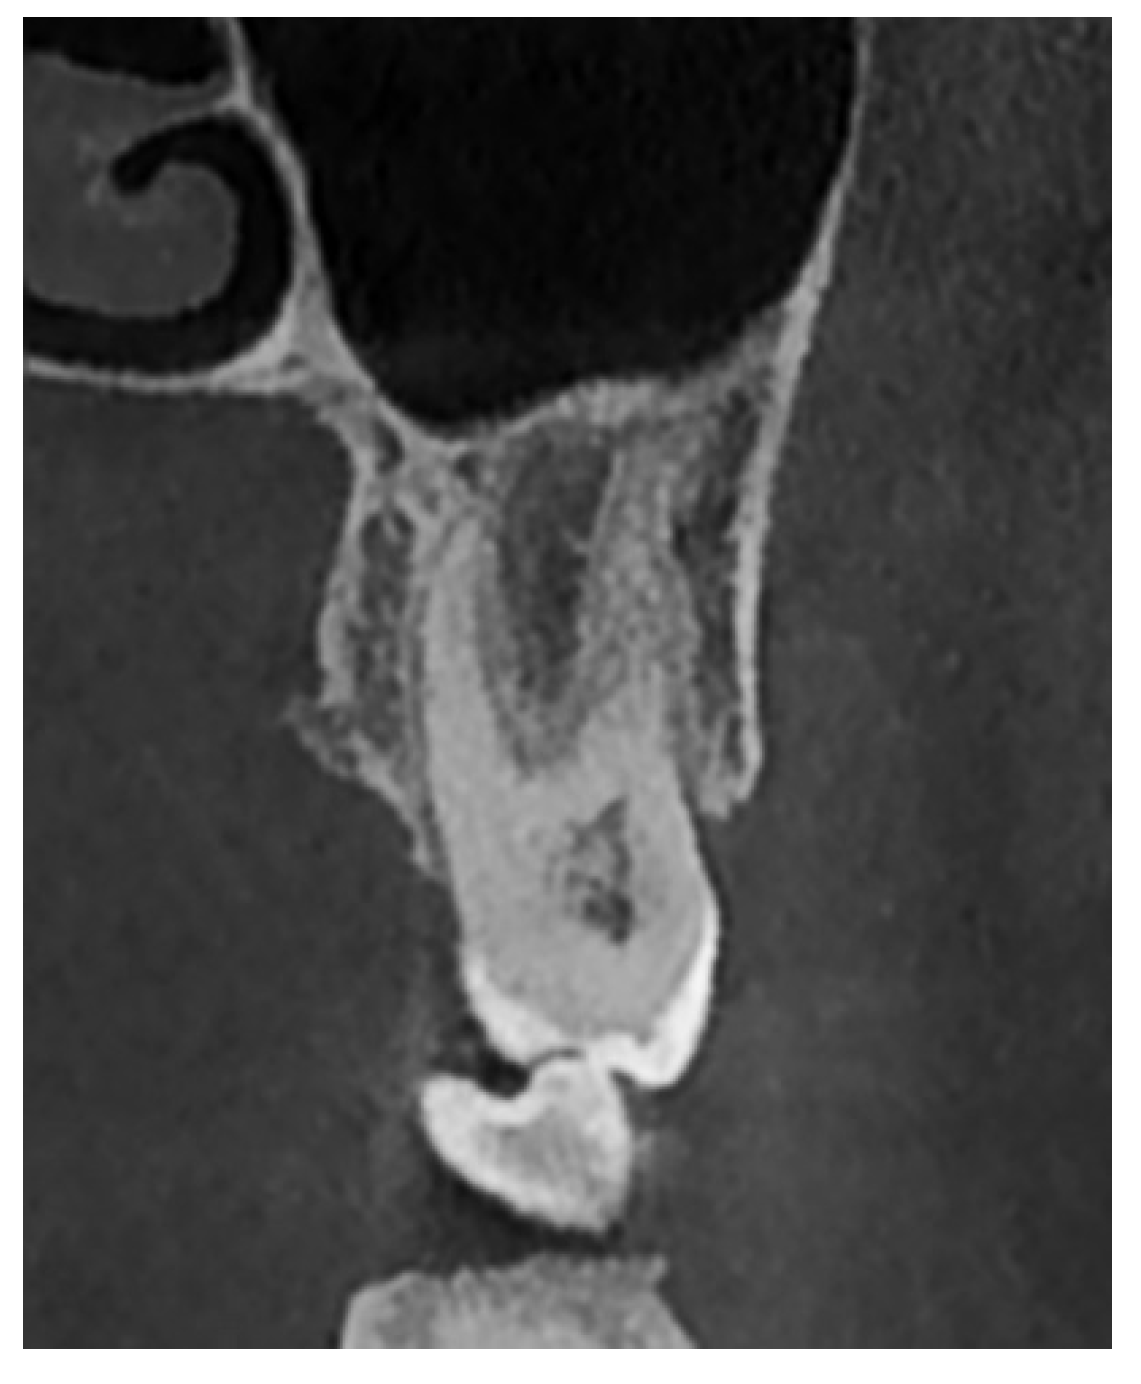

- Type III: Close relationship—the tooth root is located 0.21–2 mm from the sinus floor (Figure 4).